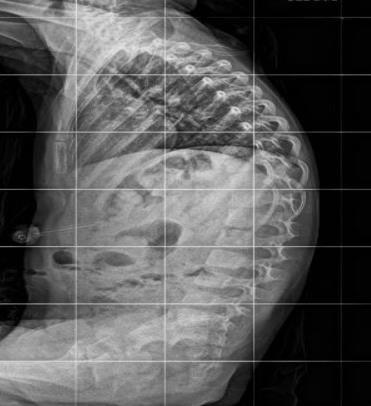

Scoliosis

Scoliosisoccursin20–25%ofCPpatients;riskincreaseswithseverity ofmotorimpairmentandreducedambulation.

•Functional Impact

Trunkimbalanceandpelvicobliquityaffectsitting,standing,and walking;severecurvescancauserespiratoryandskincomplications.

•Curve Progression Patterns

Curvesworsenrapidlyduringadolescenceandcontinuepost-skeletal maturityif>50 ,especiallyinnon-ambulatorypatients.

•Curve Types

Group1:ambulatory,idiopathic-likecurves.

Group2:non-ambulatory,longcollapsingcurveswithpelvicobliquity.

•Conservative Management

Includesseatingadaptationsandspinalbracestoimprovepostureand delaysurgery,thoughtheydon’thaltprogression.

•Surgical Indications & Outcomes

Indicatedforcurves>45–50 ,rapidprogression,orfunctionaldecline.

Goal:stable,balancedspinetoenhancequalityoflife.